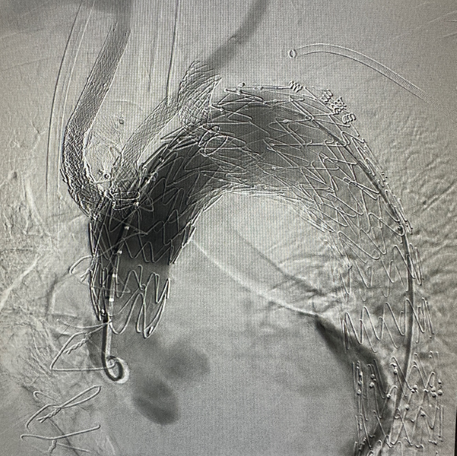

Hector™ Multi-Branch Thoracic Stent Graft System

Hector™ Multi-Branch Thoracic Stent Graft System is intended to be used to treat aortic arch lesions requiring reconstruction of the three supra-aortic branches with ≥20mm healthy landing zone proximal to the lesions, as prescribed by the physician. The device restores aortic flow through the stent graft intimal lumen and maintaining aortic arch triple-branch perfusion.